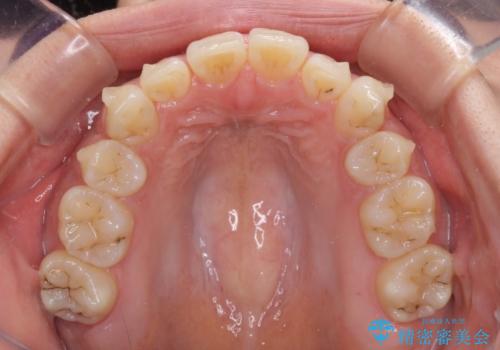

- 以前の矯正治療の後戻りにより、上下の前歯がでこぼこになってしまったことを気にして来院された患者様です。

口元がこれ以上突出することなく前歯の叢生が改善できるよう、歯と歯の間を削ってスペースを獲得し、インビザラインを用いて整えていくこととしました。

目安の装着時間である1日22時間をしっかりと実践してくださり、半年強という短期間で治療を終えることができました。